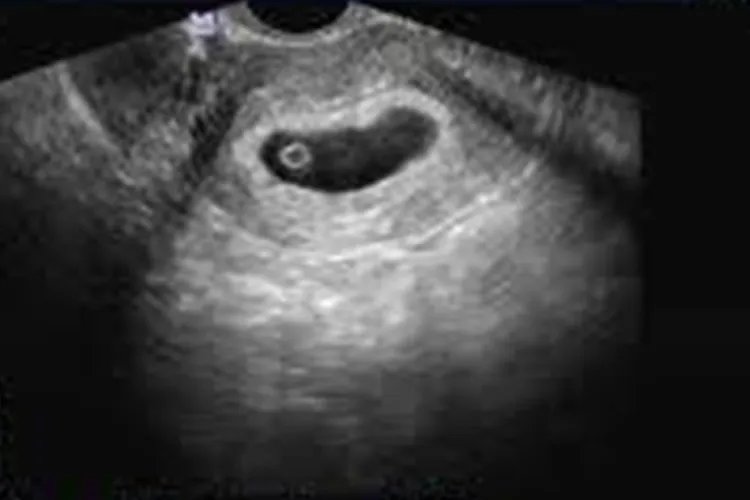

的有关信息介绍如下:概述怀孕50天胎儿还没有成形,B超下可见宫腔内有圆形或椭圆形孕囊。怀孕50天胎儿容易受到外界影响,孕妇需做好自身防护。形态怀孕50天时,即孕7周左右,还处于孕囊阶段,B超下可见宫腔内形成圆形或椭圆形孕囊,同时可见到胚芽和原始心管搏动。此时胎儿容易受到外界任何干扰,引发严重畸形甚至死亡。随着胎儿的生长,直到8周末,胎儿才初具人形,头大,占整个胎体近一半,能分辨出眼、耳、鼻、口、手指及足趾,心脏四腔结构已经形成。